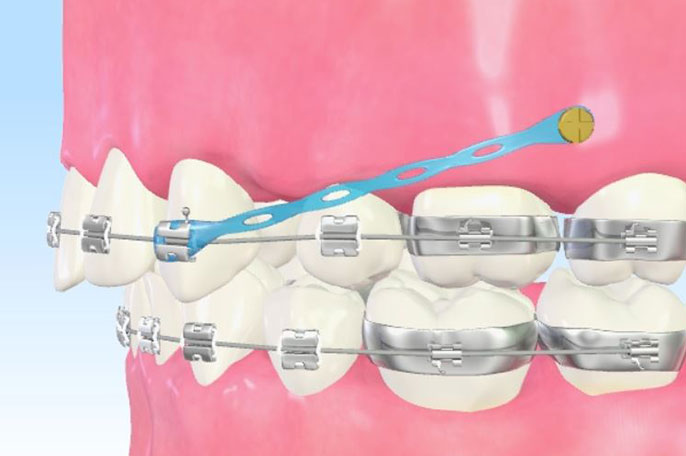

歯科矯正用アンカースクリュー

矯正具を固定するために、アンカースクリュー(微小なチタン製のネジ)を顎の骨に埋入する矯正手術を行います。

動かしたい歯のみに力を加えることができるので、倒れてしまった歯を起こしたり、ガミースマイル(笑った際に歯ぐきが目立って見えること)の改善など、通常の矯正では困難な症例にも活用することができます。

<歯科矯正用アンカースクリュー>

診療区分:自由診療

費用:アンカースクリュー1本 22,000円(税込)

※症例によって必要な本数が変わります。